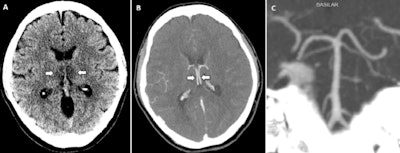

CT and MRI imaging showed the following:

- Head CT images showed symmetric hypoattenuation within the bilateral medial thalami with a normal CT angiogram and CT venogram.

- Brain MRI images showed T2-weighted and fluid-attenuated inversion recovery (FLAIR) hyperintensity within the bilateral thalami, medial temporal lobes, and subinsular regions with areas of hemorrhage, as well as rim enhancement on postcontrast images.